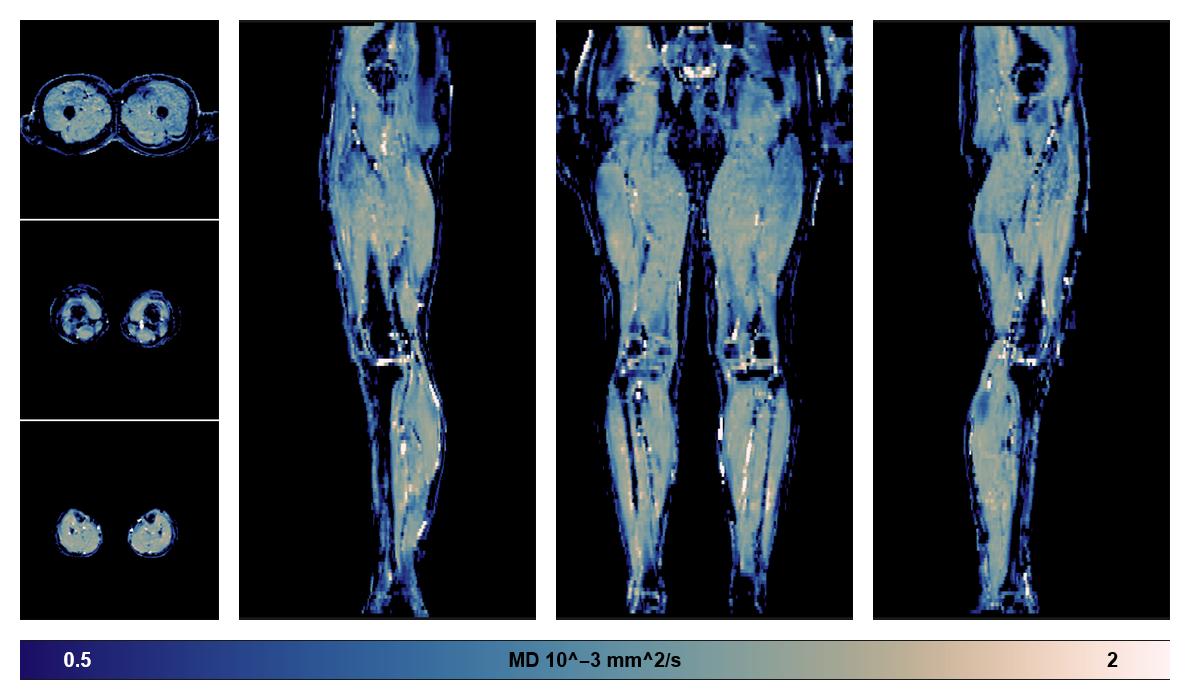

• Mean diffusivity

IVIM corrected whole leg muscle mean diffusivity obtained from diffusion tensor imaging.